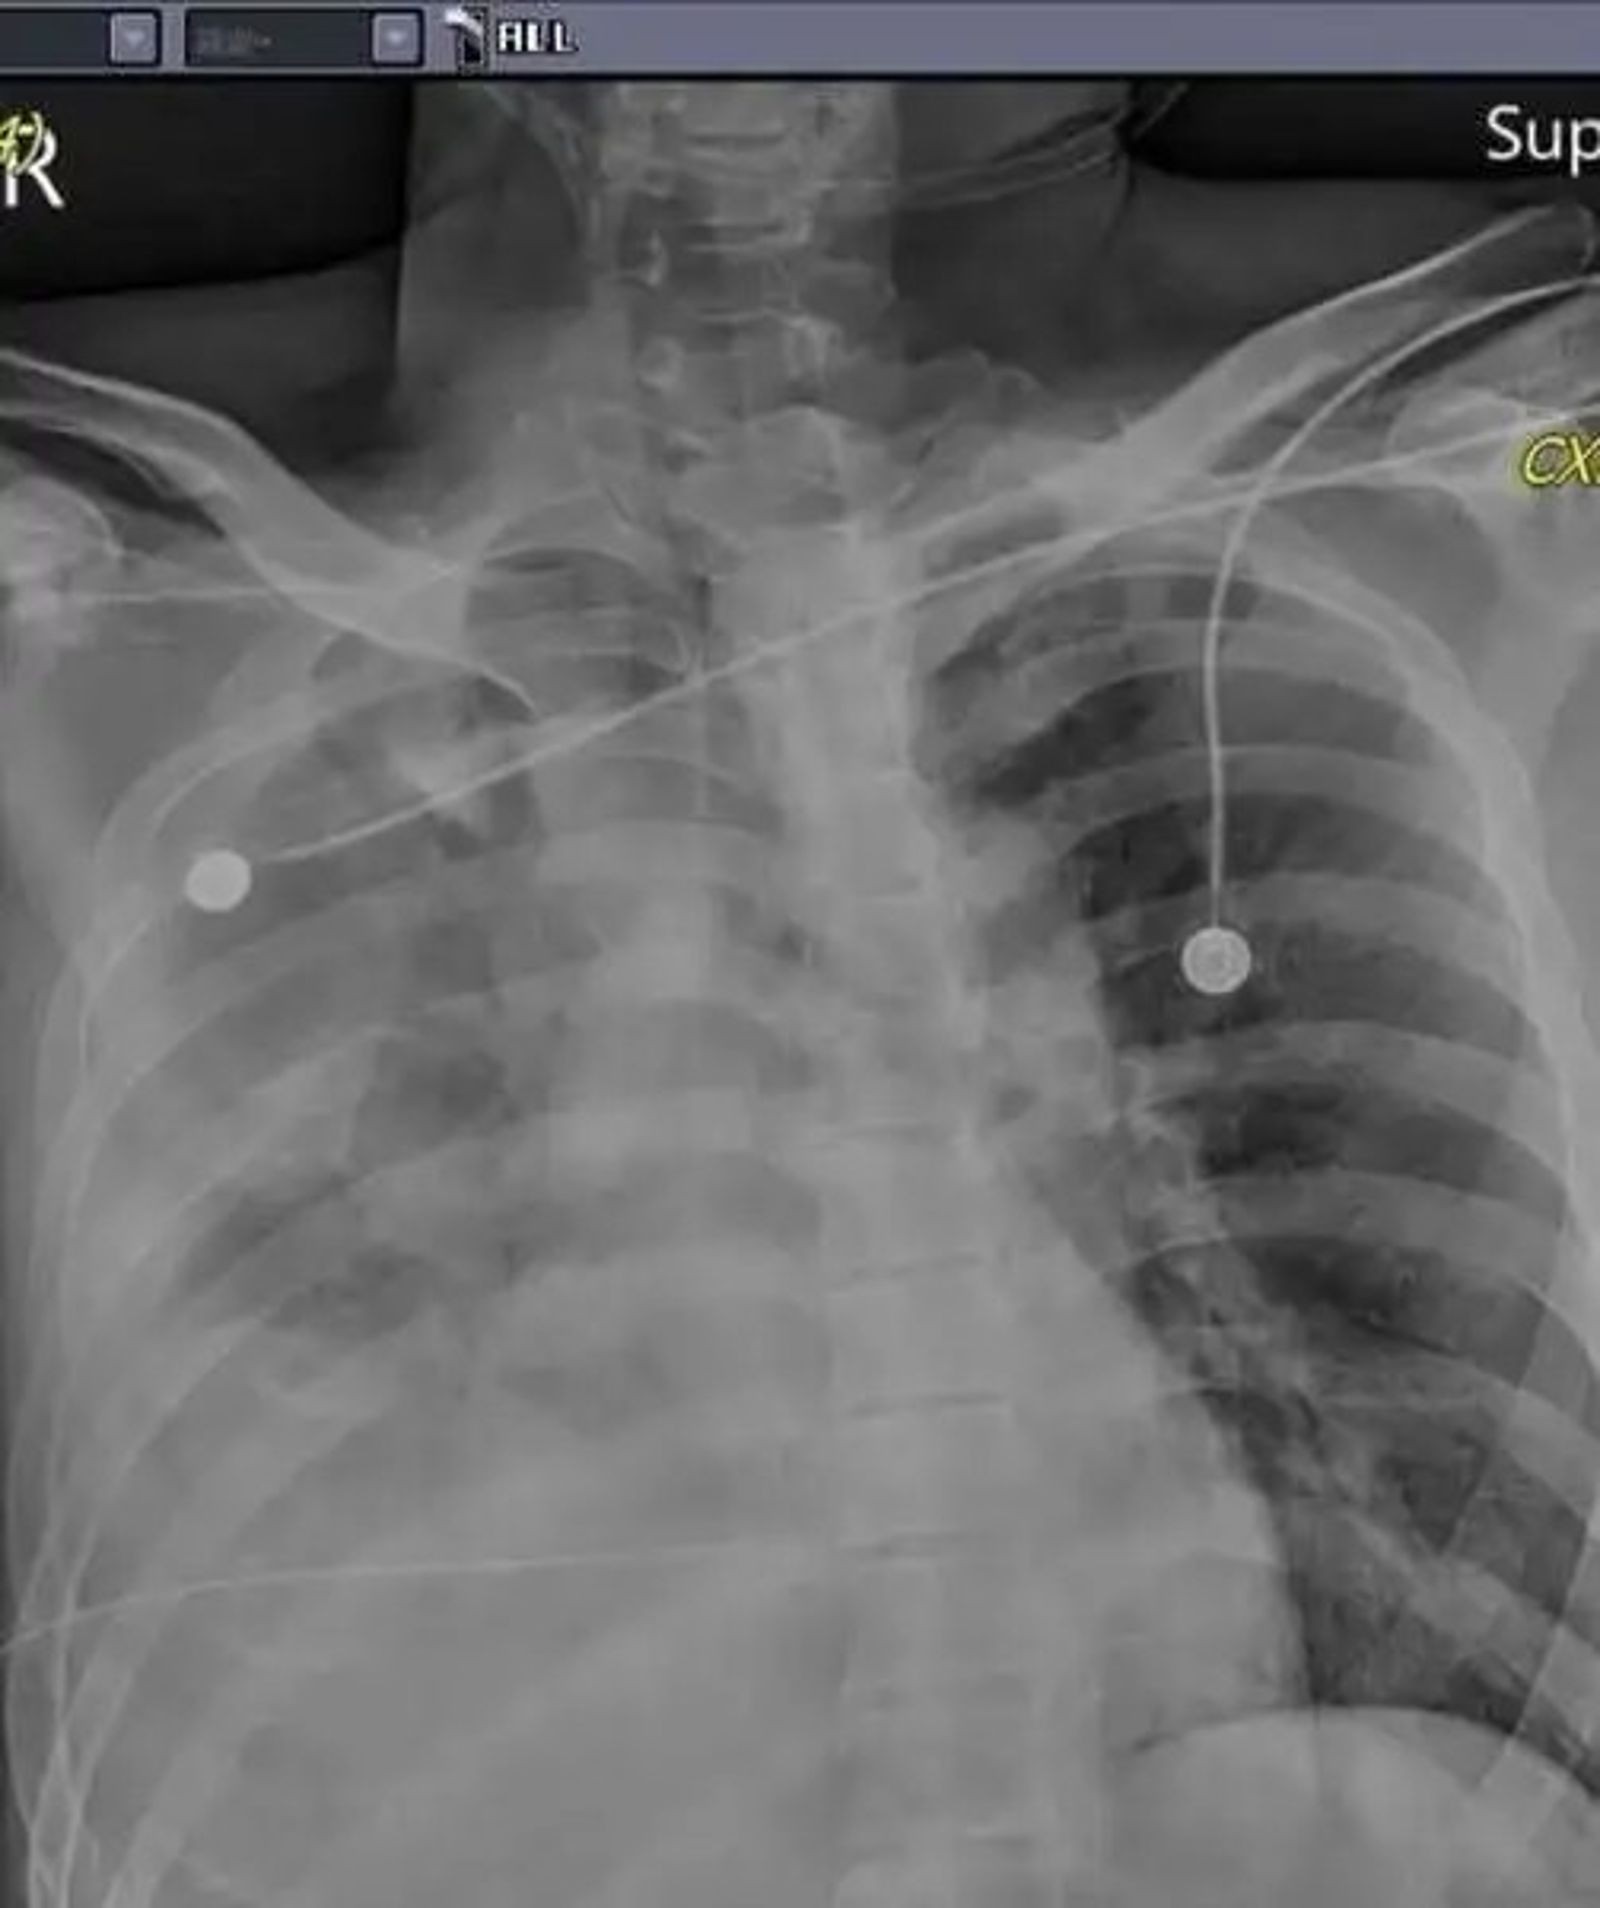

馮醫師指出,當他趕到急診室時,林男胸口、右上腹與背部皆有深可見骨的穿刺傷,「真的是傻眼,是怎樣的深仇大恨?」原以為只是氣血胸,但置放胸管後仍持續出血,情況危急。

當晚胸腔外科與一般外科醫師緊急聯手開刀,術中發現肺臟破裂引發氣血胸,橫膈膜與肝臟也被利刃刺穿,造成大量出血。醫療團隊緊急輸血3、4000cc搶救,才穩住林男生命。

所幸經手術搶救後,林男目前生命徵象穩定,雖仍插管在加護病房觀察,但3日上午巡房時已能清醒與醫護致意。馮啟彥表示,一般成人血量約5000cc,林男手術中幾乎輸掉近八成血量,能撿回一命實屬奇蹟。